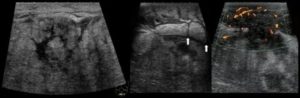

- УЗИ (ультразвуковое исследование). С его помощью можно точно определить размер и местоположение серомы. Применяется для диагностики осложнения на ранних стадиях.